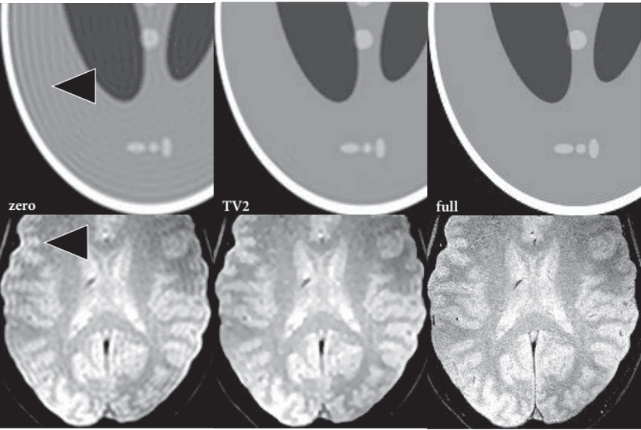

2. 图像去伪影方面:

利用传统滤波方法、深度学习方法,减轻由于患者主客观原因、设备的软硬件原因、外界的环境干扰因素等引起的伪影对图像质量的影响,使扫描图像质量能够满足临床诊断的需要。

全变分约束外推:对于超出测量部分的K空间数据,利用分段常数对象的简单假设进行推断,利用此方法可以显著减小截断伪影且不影响图像分辨率。

12.png